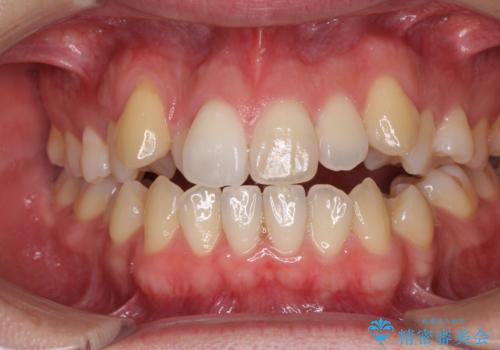

[ 前歯開咬 ] 前歯が噛んでいない マウスピース矯正治療

担当医 大元洋佑

![[ 前歯開咬 ] 前歯が噛んでいない マウスピース矯正治療の症例 治療前](https://seimitsushinbi.jp/wp/wp-content/uploads/2022/11/IMG_4669-500x350.jpg?v=1668218426)